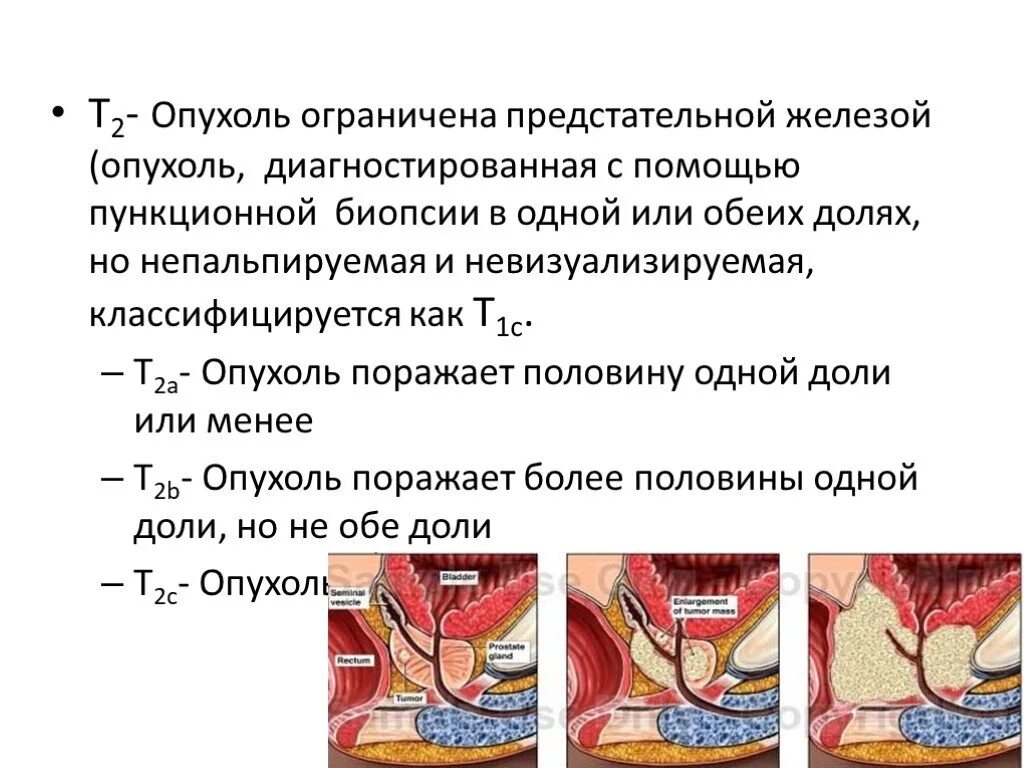

Опухоль предстательной железы. Опухоль простаты симптомы. Злокачественное новообразование предстательной железы. Фиброз предстательной железы ТНМ классификация предстательной железы. Опухоли предстательной железы классификация. Классификация степени аденомы простаты. TNM предстательная железа

ТНМ классификация предстательной железы. Опухоли предстательной железы классификация. Классификация степени аденомы простаты. TNM предстательная железа Карцинома предстательной железы. Cancer предстательной железы. Раковые клетки простаты

Опухоли простаты классификация. Классификация аденомы предстательной железы по стадиям. Стадии ТНМ при предстательной железы. Карцинома 4 степени предстательной железы

Опухоли предстательной железы классификация. Злокачественное новообразование предстательной железы. Опухоль предстательной железы т2. Стадии ЗНО предстательной железы

Опухоли предстательной железы классификация. Злокачественное новообразование предстательной железы. Опухоль предстательной железы т2. Стадии ЗНО предстательной железы Опухоль предстательной железы пса. Что такое РПЖ предстательной железы. Степени опухолей простаты. Предрак предстательной железы